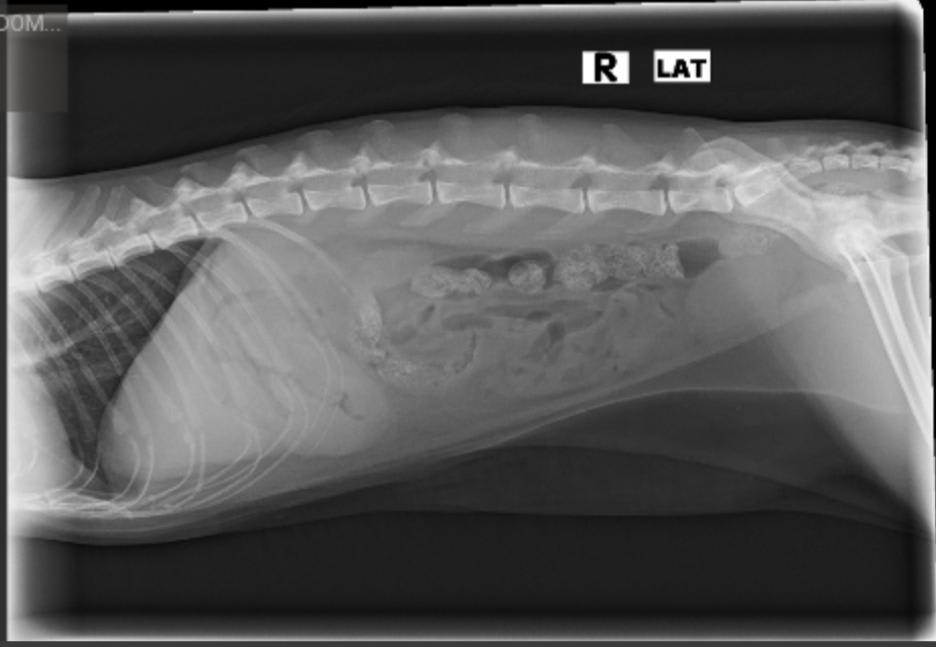

Pet's info: Cat | American Shorthair | Male | neutered | 6 years and 8 months old | 9 lbs

I took my cat to the vet Friday. The vet thought he had an intestinal adhesion, but called back saying it was inoperable lymphoma. I do not have the ultrasound images. From the x-rays can you identify the mass? Could it be anything else?

So very sorry for you loss of Indy. My condolences. I can see on the x-ray what the vet was thinking may have been an adhesion. I cannot tell you what it is though just by looking at the x-ray. The only way to know what the mass is/was is to have sent it to a laboratory for histopathology. Masses can be any number of things. I can tell you that lymphoma is quite common in cats. Unfortunately, we are not going to be able to help you with this via the internet as we were not there to see what happened. If you wanted a definitive diagnosis then a necropsy (autopsy) would have been needed with tissue samples sent to the lab for analysis.